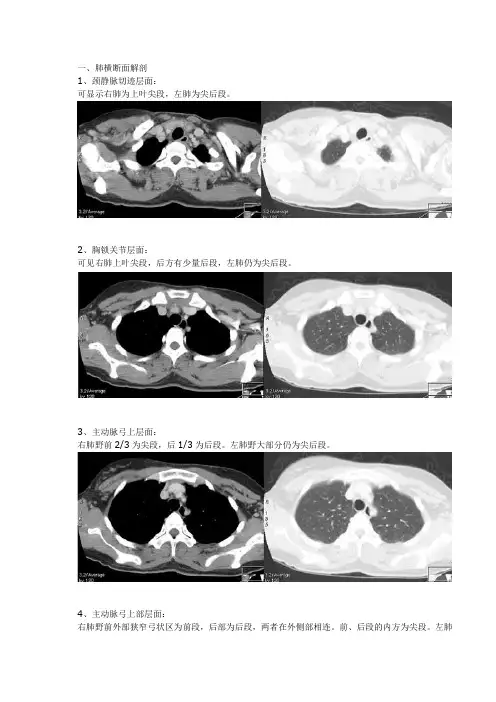

一、肺横断面解剖1、颈静脉切迹层面:可显示右肺为上叶尖段,左肺为尖后段。

2、胸锁关节层面:可见右肺上叶尖段,后方有少量后段,左肺仍为尖后段。

3、主动脉弓上层面:右肺野前2/3为尖段,后1/3为后段。

左肺野大部分仍为尖后段。

4、主动脉弓上部层面:右肺野前外部狭窄弓状区为前段,后部为后段,两者在外侧部相连。

前、后段的内方为尖段。

左肺野前1/3为前段,中后部大部分为尖后段,尖后段后方边缘已出现少许下叶背段。